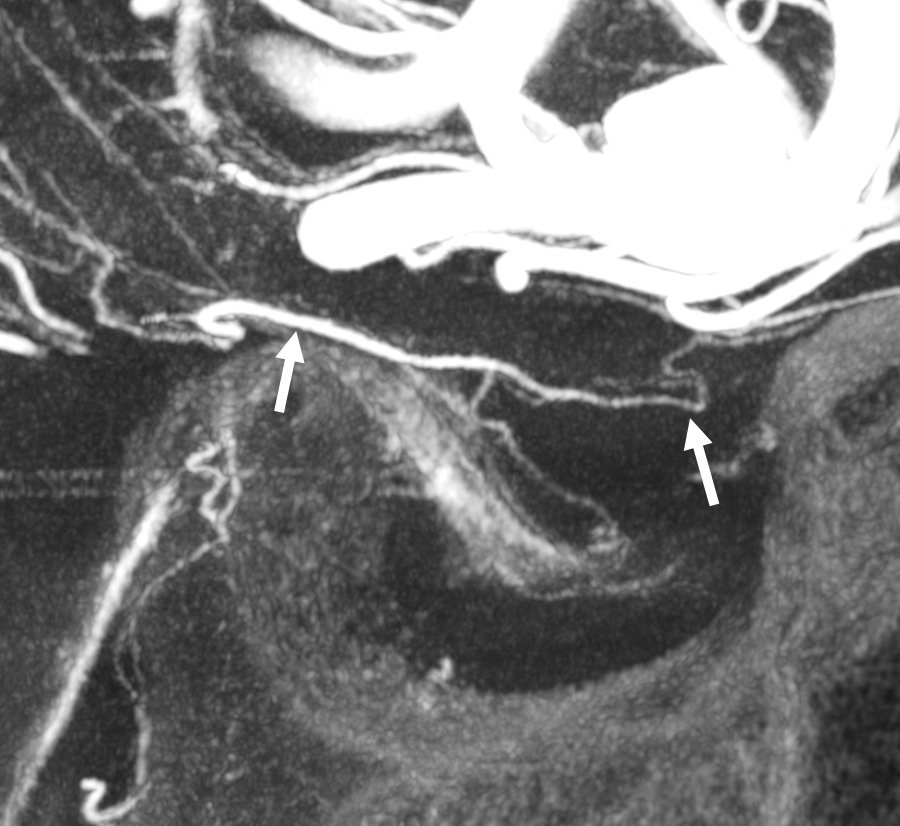

Case courtesy Dr. Eytan Raz — here is a beautiful example of a very dominant superior hypophyseal artery (arrow) supplying the posterior hypophysis (arrowhead), with a correspondingly small inferior hypophyseal contribution from the MHT (dashed arrow)

Cross eye stereo

View from the back — again small inferior hypophyseal, big superior hypophyseal — balance again… See the beautiful vascular ring of the posterior pituitary — the connecting it with the contralateral side

Cross-eye stereo

MIP image shows the sella nicely — and helps prove its posterior pituitary

Pure arrowless images — easier to steal…

Of course, there is an aneurysm here — the branch point camp would point out how this larger than usual branch is a setup for aneurysmal formation. Naturally…